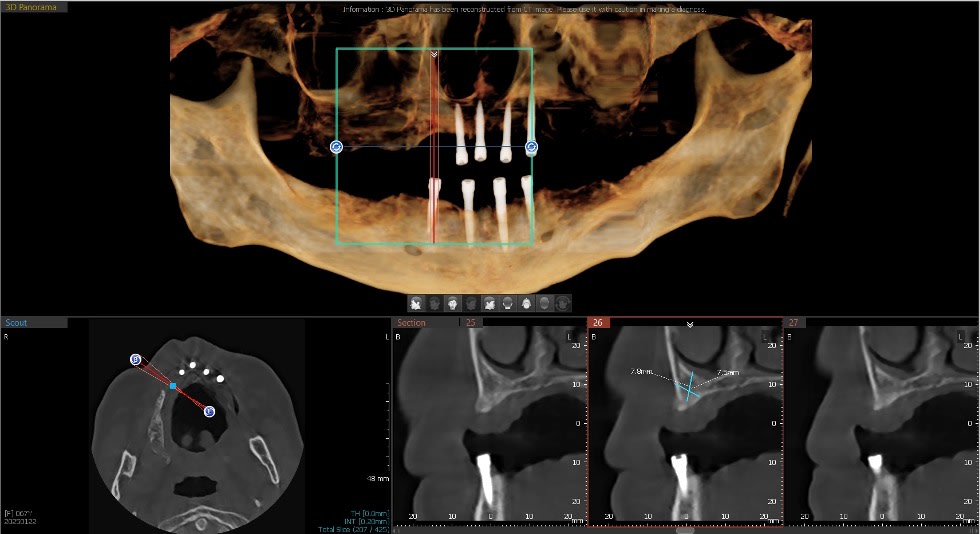

A 67-year-old female patient had a chief complaint of being unhappy with a previously fabricated full palate covered LOCATOR overdenture. The implant positioning was adequate, but the AP spread was not suitable to retain a palateless overdenture nor a fixed implant prosthesis. Five implants had apparently been placed previously but the maxillary right implant had not integrated properly and was removed prior to her evaluation in this practice. There were no significant health issues or medication concerns. She requested “permanent teeth” to improve her quality of life, function, and esthetics. The periodontal health around the existing dental implants was good, with no significant concerns. Figure 1 illustrates the esthetics created by the recently made maxillary and mandibular LOCATOR overdentures. The dentures provided some increased stability and function, but the patient’s concern was that they were not what was promised (Figure 2). CBCT analysis indicated some compromised bone contours where the maxillary right posterior implant has been avulsed (Figure 3). A newly placed fifth dental implant was needed to support any fixed prosthesis in this compromised edentulous arch. A new 3.5 mm x 10 mm HT™ dental implant (Glidewell, glidewelldental.com) was strategically positioned in front of the large maxillary sinus to provide distal support for the final prosthesis (Figure 4).

The 3.5 mm x 10 mm HT dental implant successfully integrated in the available hard tissue in the maxillary right second bicuspid area. The implant had been allowed to integrate for approximately 4 months and the patient wore the existing fabricated full palatally covered implant-retained LOCATOR overdenture during the healing period.

Due to the angulation of the implant placement, a 15-degree angled LOCATOR abutment was placed (Figure 5 and Figure 6). Angulation pins were passively placed into the LOCATOR abutments to determine proper spacing (Figure 7). The existing maxillary and mandibular appliances were scanned (fastcscan io™ with Medit® i700®, Glidewell) for the laboratory to design the initial try-in appliance prior to milling of the final zirconia LOCATOR FIXED® prosthesis (Figure 8). LOCATOR scan bodies were placed, and the LOCATOR level digital impression was made (Figure 9).